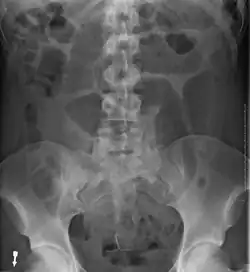

-

Plain X ray of a cecal volvulus -